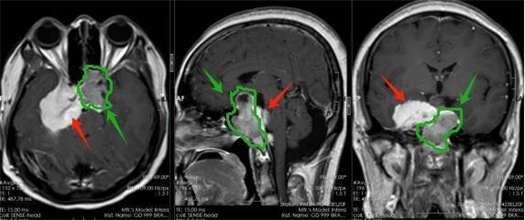

术前影像,其中绿色箭头考虑为垂体瘤,红色箭头考虑为脑膜瘤。

8月初,萍姐来到广东三九脑科医院。鲁明接诊后发现,患者鞍区占位约3厘米,压迫视神经引起视力下降,考虑为垂体瘤;蝶骨嵴、海绵窦、斜坡占位约5.2厘米,引起颅高压症状,考虑为脑膜瘤。尽管两个肿瘤相邻,但体积均较大且位置特殊,难以一次性切除。因此,萍姐做了两次手术才成功将肿瘤切除。